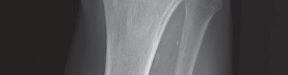

2. التصوير بالأشعة السينية (X-ray):

تُعد الأشعة السينية هي الأداة التشخيصية الأساسية لتقييم خشونة الركبة. يلتقط الأستاذ الدكتور هطيف صورًا للركبة من زوايا مختلفة، بما في ذلك صور الوقوف (Weight-bearing X-rays)، والتي تُظهر المفصل تحت تأثير وزن الجسم الطبيعي. تُظهر الأشعة السينية ما يلي:

- تضييق المسافة المفصلية: خاصة في الجانب الإنسي للركبة، مما يشير إلى تآكل الغضروف.

- تكون النتوءات العظمية (Osteophytes): وهي نتوءات عظمية صغيرة تتشكل حول حواف المفصل نتيجة للتآكل.

- تغيرات في كثافة العظام: مثل التصلب تحت الغضروفي (Subchondral Sclerosis).

- درجة الانحراف التقوسي: قياس الزوايا المحورية للساق لتحديد مدى التقوس بدقة.